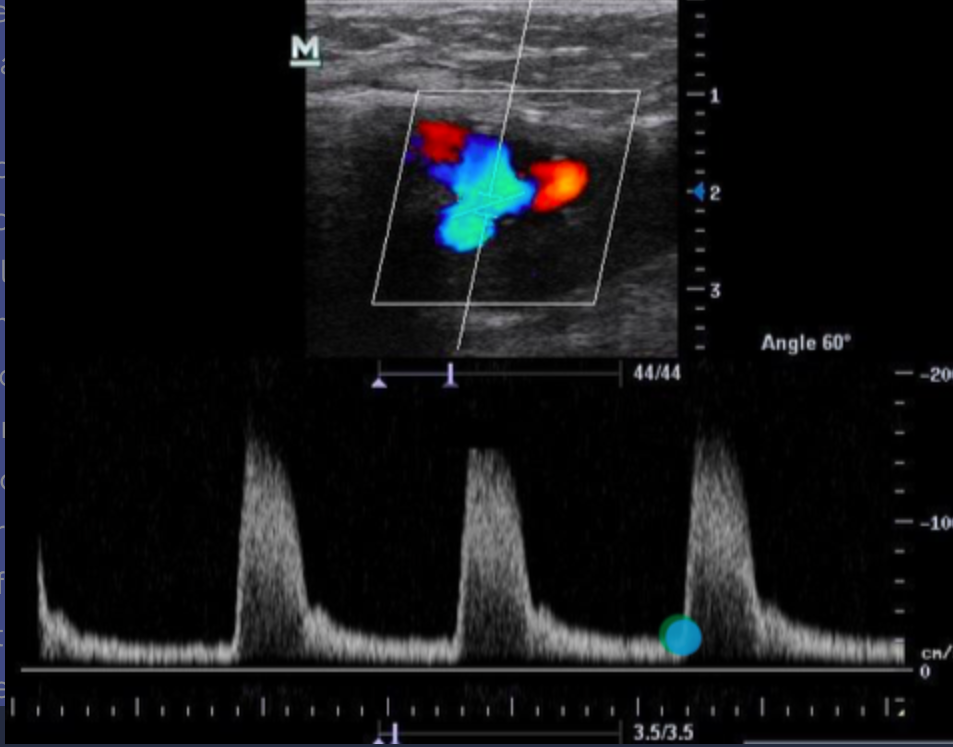

Which of the following statements best describes the reason why there is an absence of color flow in the vessel on the image?

a. The ultrasound beam is parallel to the motion of the blood so non flow is detected

b. the color Doppler gain is set too low to detect the slower flow at the curve in the vessel

c. there is an occlusion present. flow is demonstrated proximal to the lesion with collateral flow filling the distal portion of the vessel

d. the ultrasound beam is perpendicular to the motion of blood so no flow is detected

the ultrasound beam is perpendicular to the motion of blood so no flow is detected